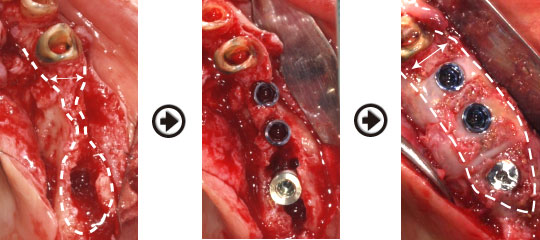

インプラント治療(GBRと併用)症例

骨が少ない場合は、厚みや高さを増大(GBR)させた、しっかりとした骨の中に、 インプラントを理想的な位置に植立することがインプラントを長持ちさせる為には、重要です。

インプラント治療(GBR)過程